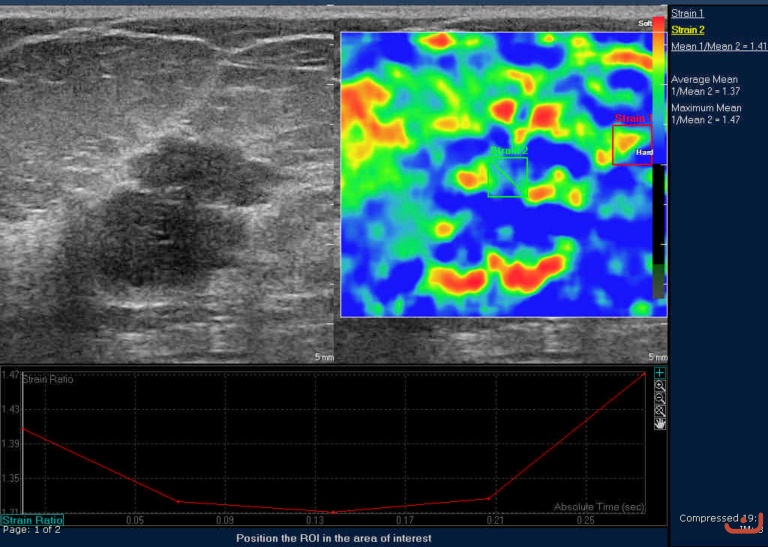

Case 43-E1

Malignant solid mass